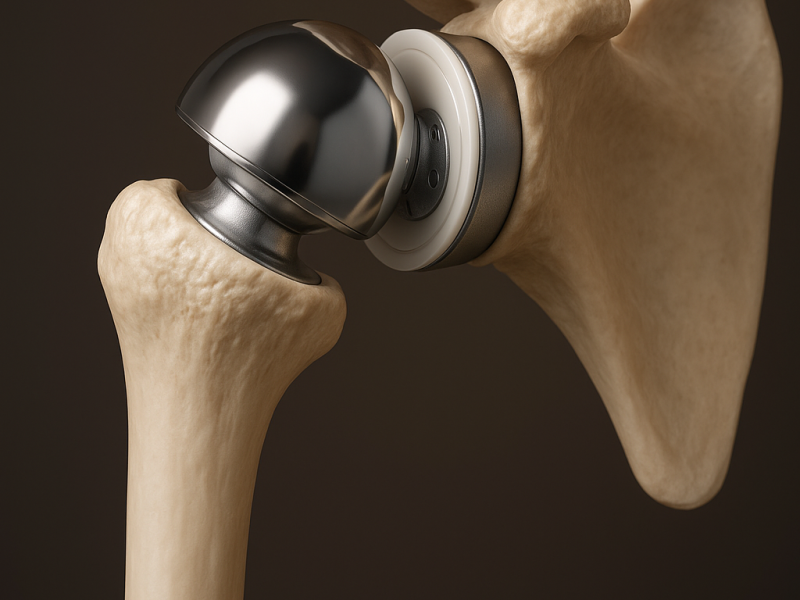

Il dolore all’anca può limitare ogni aspetto della vita quotidiana: camminare, salire le scale, dormire serenamente, praticare attività fisica.La protesi totale di anca rappresenta oggi una soluzione sicura, efficace e definitiva per ritrovare libertà di movimento e qualità di vita.Grazie a tecniche chirurgiche evolute e a un percorso altamente personalizzato, accompagniamo il paziente verso un recupero stabile, rapido e duraturo.

Tecniche Chirurgiche Avanzate

Accesso Laterale e Postero-Laterale

La scelta dell’accesso chirurgico è un momento fondamentale dell’intervento e viene effettuata in modo mirato, in base alle caratteristiche anatomiche e agli obiettivi funzionali del paziente.

Accesso Laterale

Questa tecnica garantisce:

• Elevata stabilità dell’impianto

• Ottimo controllo dell’allineamento protesico

• Sicurezza nel decorso post-operatorio

• Recupero progressivo e controllato

È particolarmente indicata nei pazienti in cui è prioritario massimizzare la stabilità dell’articolazione.

Accesso Postero-Laterale

Tecnica consolidata e ampiamente utilizzata a livello internazionale, offre:

• Eccellente esposizione dell’articolazione

• Precisione nel posizionamento delle componenti

• Rispetto delle strutture muscolari

• Recupero funzionale efficace

La ricostruzione accurata dei tessuti garantisce stabilità e ottime performance nel tempo.

Un Percorso Personalizzato

Ogni intervento è preceduto da un’attenta valutazione clinica e da una pianificazione pre-operatoria dettagliata. Nulla è lasciato al caso.

L’obiettivo è offrire al paziente la soluzione più adatta alle sue esigenze, riducendo il dolore e favorendo un ritorno rapido e sicuro alle attività quotidiane.

Recupero Rapido e Controllato

Grazie a protocolli moderni di gestione del dolore e a un programma riabilitativo mirato:

• La mobilizzazione inizia precocemente

• Il dolore è efficacemente controllato

• Il recupero della forza e della mobilità è graduale ma costante

Il paziente viene seguito in ogni fase, dall’intervento fino al completo ritorno all’autonomia.

Ritrova la Tua Libertà

La protesi totale di anca non è solo un intervento chirurgico:

è un nuovo inizio.

Affidarsi a un approccio specialistico significa scegliere sicurezza, esperienza e attenzione alla persona.

Per tornare a camminare con fiducia.

Per tornare a vivere senza dolore.